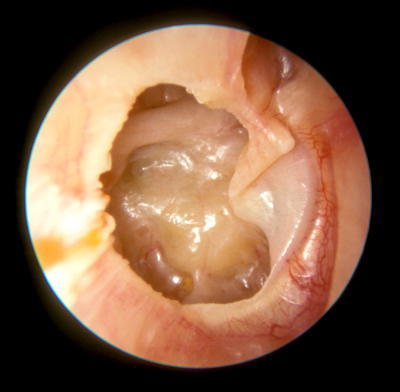

Question 1

Question

Describe the ear!

Answer

Bulging Tympanic Membrane

Acute Otitis Media

Distorted cone of light

Left ear

Treat with penicillin, amoxycillin, co-amoxiclav

Caused by: Streptococcus pneumoniae, haemophilus influenzae, moraxella catarhalis, GAS or S. aureus